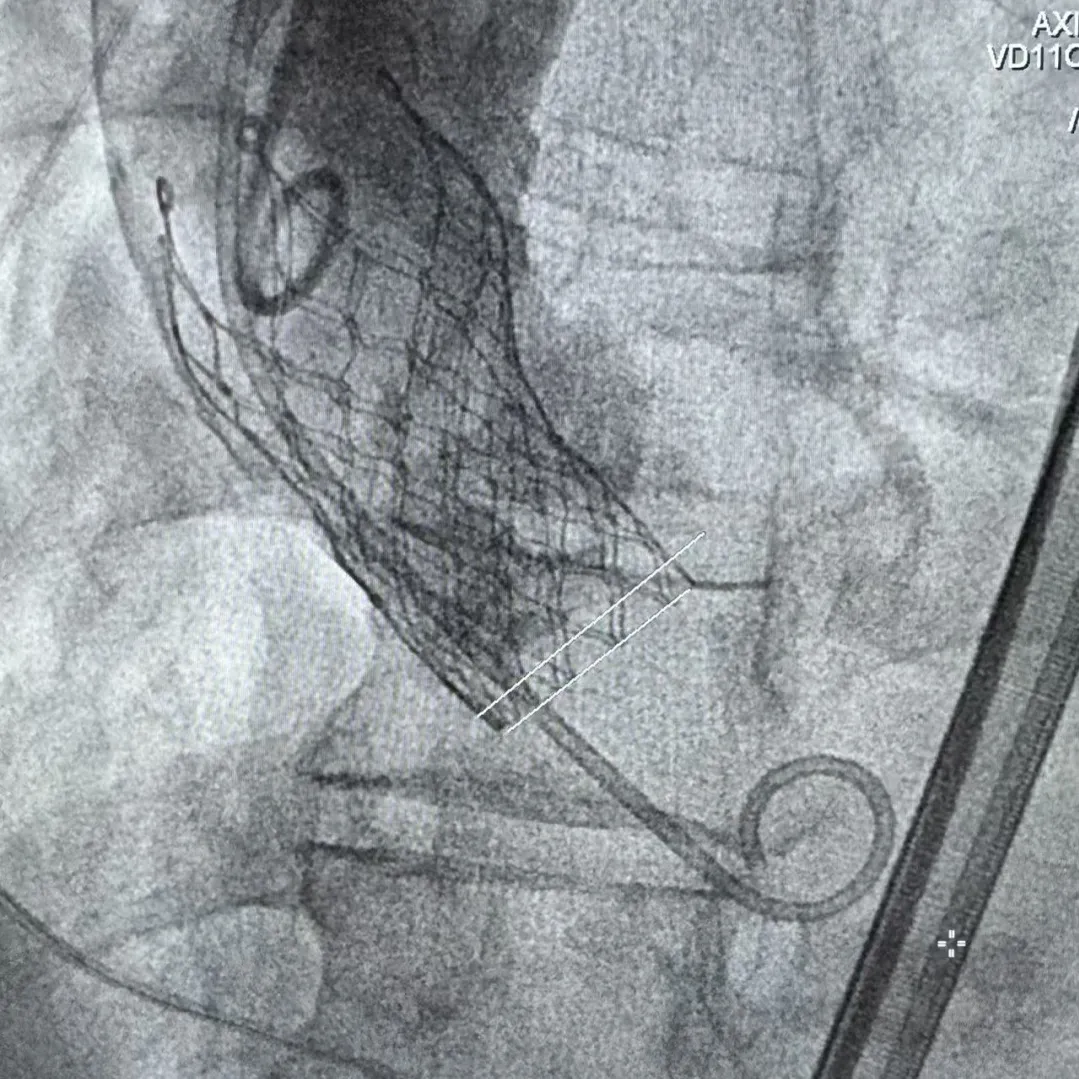

Step 5.瓣膜定位与释放:高起始位逐渐向下推送保持良好同轴性,无位移

Step 6.工作位观察:真实瓣环下方2mm,位置合适,决定释放,一次完成

Step 7.瓣膜脱钩:脱钩稳定无位移

Step 8.最终造影:真实瓣环下方3mm标准位,完全同轴,轻微反流,猪尾撤出后反流完全消失

Step 9.CuspOverlap体位验证缘对缘对齐,挂钩位于最右方,基本避开冠脉开口

Step 10.验证器械同轴性,完全同轴

瓷化升主动脉和复杂弓形一直是TAVR手术中的痛点病例,既往对于这类病例一般使用可调弯的TAVR系统辅助,此次手术使用通过性良好的自展瓣+可调弯鞘,既能满足小瓣环患者的血流动力学需求,也能大幅减小患者的手术风险。该病例既能看到Prostyle A这款预装干瓣表现了良好的通过性,在瓷化血管里推进时没有明显阻力,不用过度用力,推送十分顺畅,完全悬空通过,器械释放也很稳定;也可以看到可调弯鞘对手术过程的辅助作用,实际上对术者来说我们过往的重点都放在主要的耗材本身,辅助的耗材是否搭配起来好用,对手术的帮助也非常重要,这次手术最终还有一个亮点就是瓣膜放下去同轴性非常好,几乎是和真实瓣环平齐,这也是搭配起来产生的优秀结果。